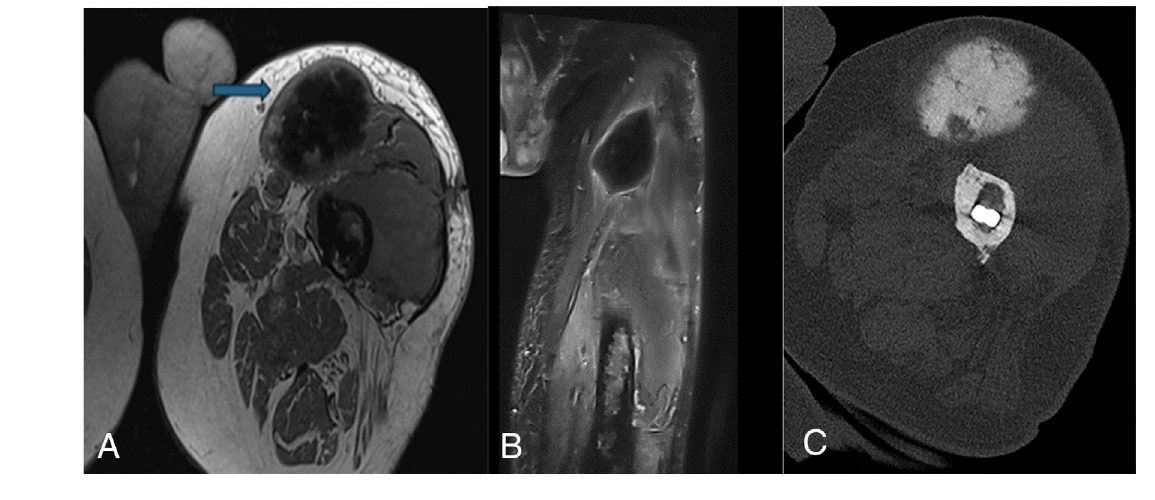

2.2 Hallazgos de imagen

- Radiografía simple: Área de destrucción ósea lítica agresiva que reemplaza la típica arquitectura pagética (hueso engrosado, desorganizado). Se pierde la cortical, aparece una masa de partes blandas asociada y puede haber fractura patológica. La reacción perióstica es rara.

- RM y TC: Confirman la extensión de la destrucción ósea y la presencia de una masa de partes blandas. La RM es esencial para planificar la cirugía.

- Imagen: Lesión osteolítica agresiva, con destrucción cortical y masa de partes blandas, dentro del campo de radiación. La radiación previa puede causar cambios óseos (osteoporosis, necrosis) que dificultan la interpretación.

- Necrosis ósea post-radioterapia: Es la entidad más importante a diferenciar. La necrosis suele ser asintomática o causar dolor leve, sin masa de partes blandas. En RM, la osteonecrosis puede mostrar el signo de la "doble línea" (dos líneas paralelas concéntricas, una hiperintensa y otra hipointensa en T2), mientras que el sarcoma se presenta como una masa destructiva con realce.

- Necrosis ósea post-radioterapia: Clave: ausencia de masa de partes blandas, signo de la doble línea en RM, no realce significativo. La biopsia muestra hueso necrótico sin células tumorales viables.